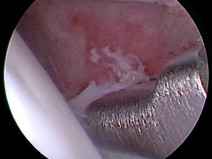

• Les bases en ophtalmologie : de l’examen oculaire aux cas pratiques

Les atteintes oculaires sont des motifs de consultation fréquemment rencontrées en médecine vétérinaire avec des répercussions potentiellement dramatiques pour la conservation de la vision ou du globe oculaire.

Savoir reconnaitre et savoir traiter ses atteintes est donc essentiel et passe par la réalisation d’un examen oculaire complet et systématique. Mais contrairement aux idées reçue...

Ophtalmologie